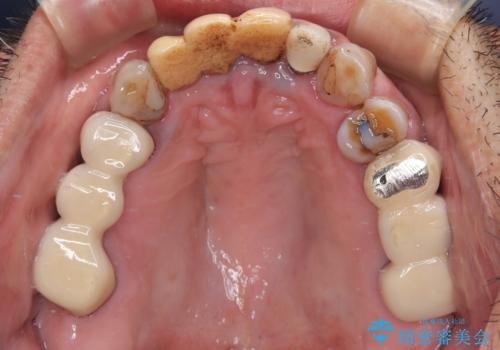

- 治療中の医院で装着した仮歯が汚れていて恥ずかしいとのことで来院された患者様です。

仮歯が不適合で歯肉が腫脹していたため、しっかりと調整した新しい仮歯にして腫れを改善した上で、オールセラミッククラウンにて補綴することとしました。

仮歯の隣の歯も詰め物の範囲が広く、仮歯をセラミックに置き換えても統一感のない口元となってしまうため、相談の結果、前歯6本をオールセラミッククラウンにて補綴治療を行うこととしました。